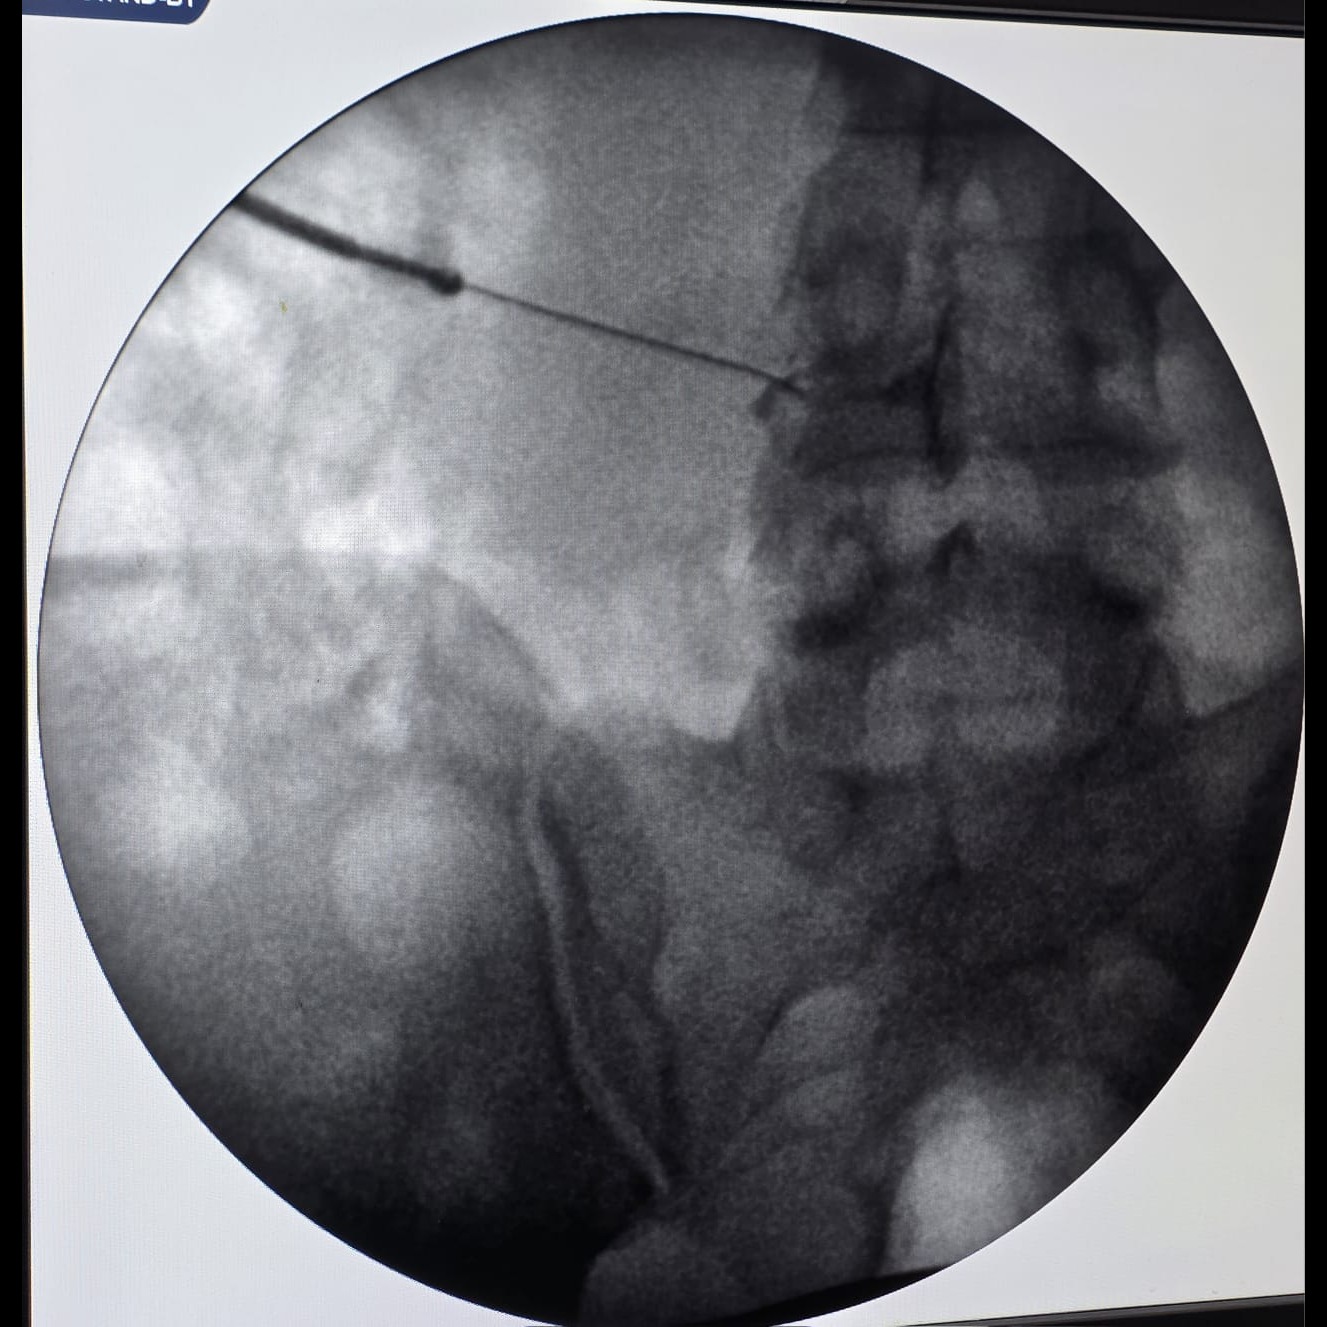

One highly effective non-surgical treatment for sciatica is the Transforaminal Epidural Steroid Injection (TFESI). This targeted procedure delivers medication directly to the inflamed nerve, providing relief and reducing the need for surgery.

It’s a minimally invasive injection of anti-inflammatory medicine (usually a steroid) near the nerve root, through the natural opening (foramen) in the spine. The procedure is done using X-ray (fluoroscopy) guidance to ensure precision and safety.